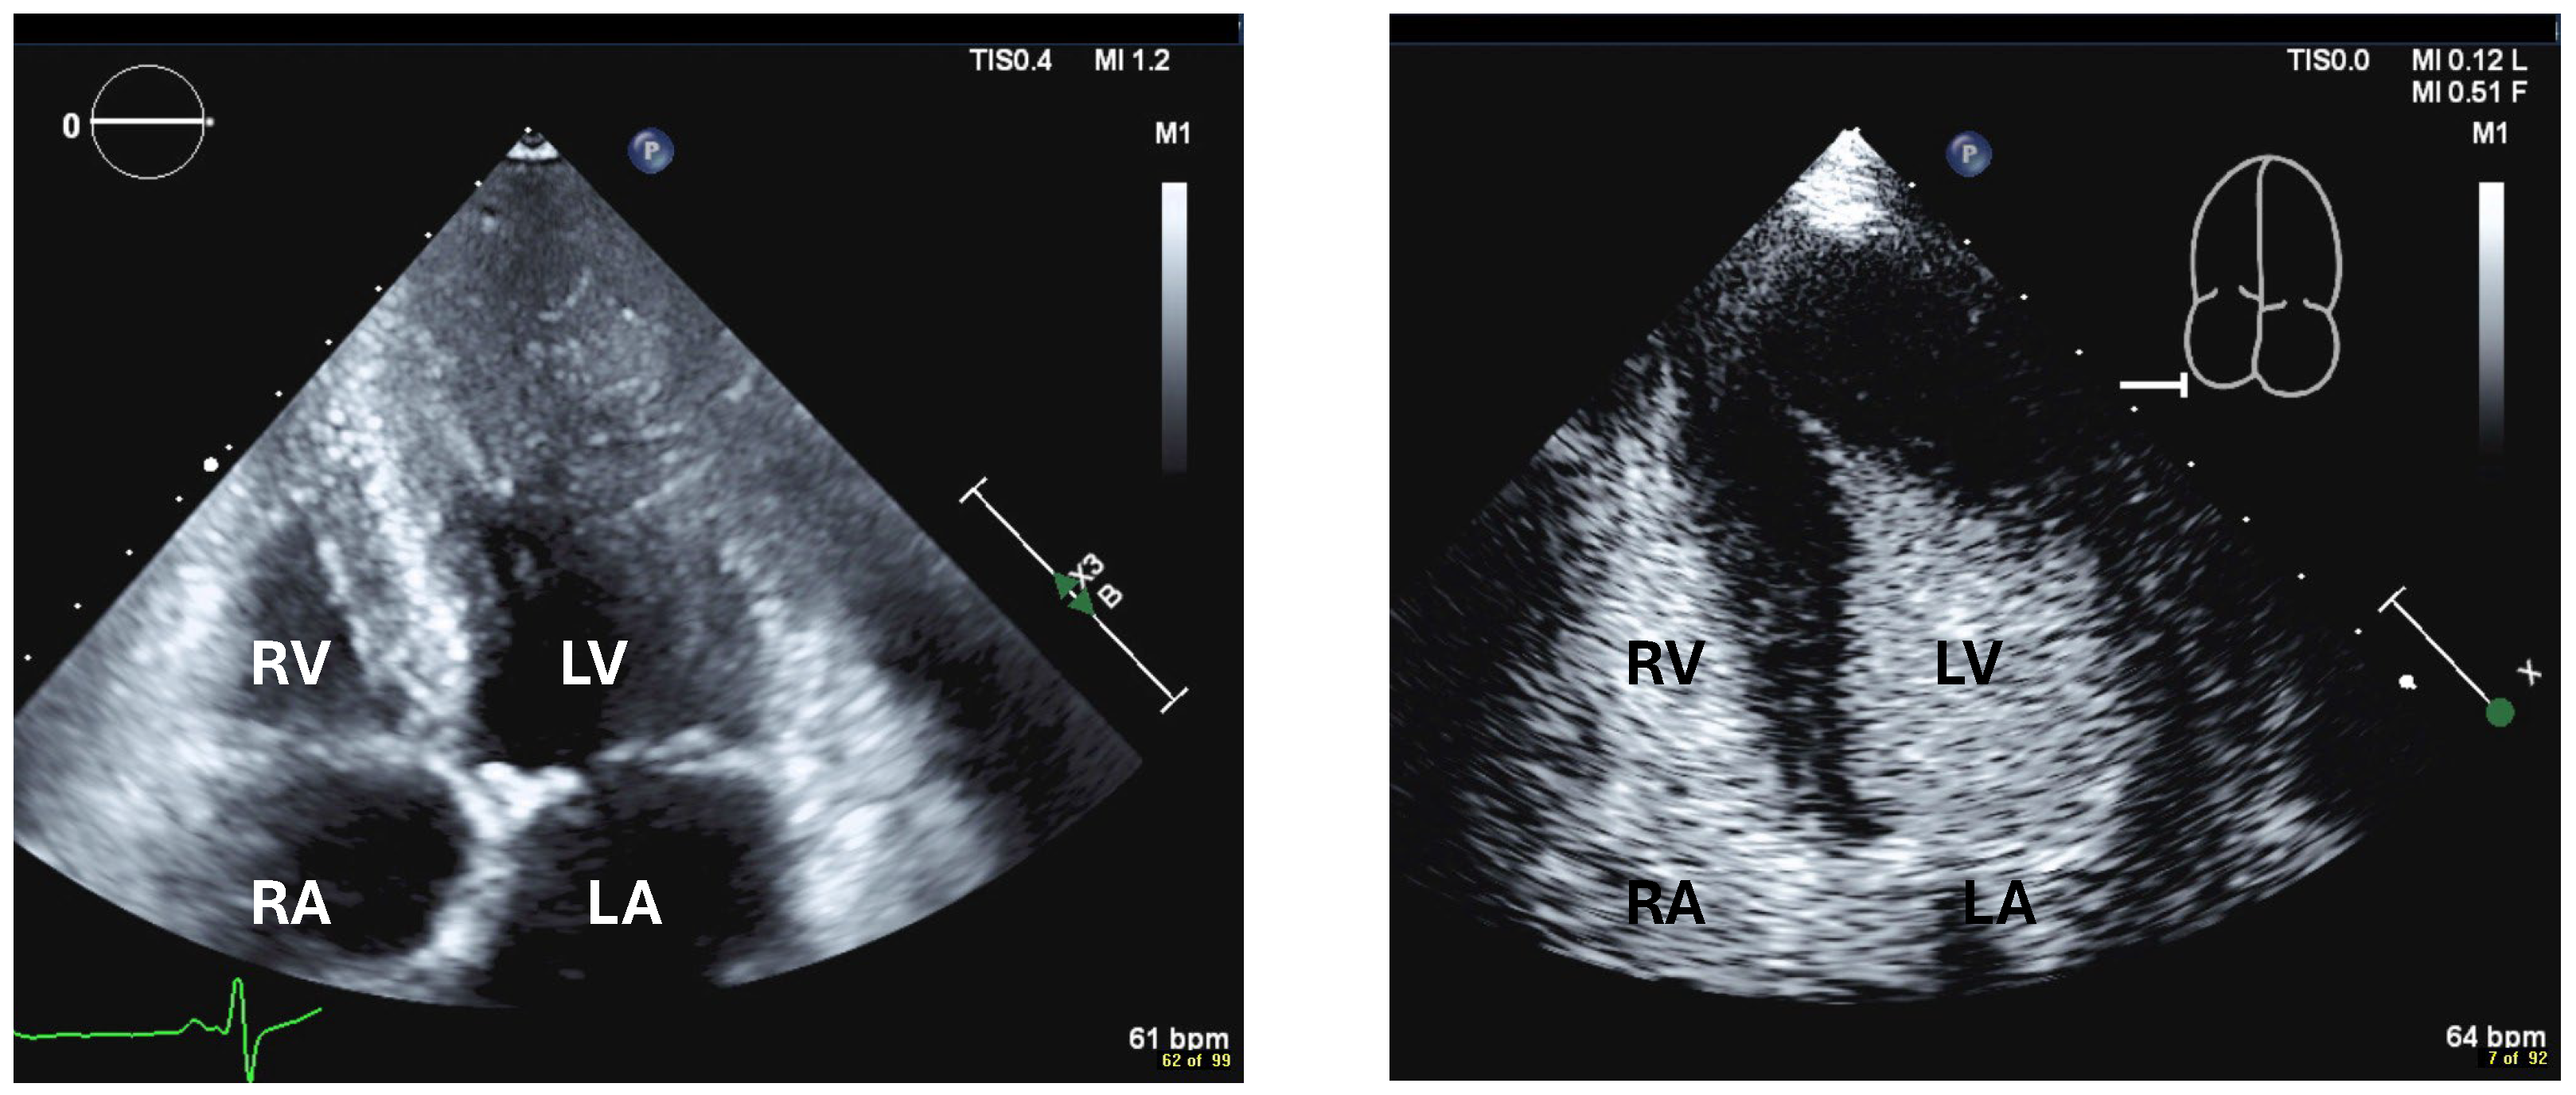

| Imaging method | Low-MI-contrast-specific imaging, additional intermediate-MI imaging in case of apical aneurysm for assessment of thrombus in the aneurysm |

| Imaging planes | Standard apical views and apical sweeps to assess the aneurysm for thrombi |

| Contrast application | Bolus injections |

| Typical finding | 1. Hourglass/ace-of-spades shape of apical LV cavity 2. Apical myocardium appears dark in late systole due to compression of the intramyocardial vessels 3. Apical aneurysms +/− thrombi in some patients |

| Alternative imaging | MRI useful for scar/fibrosis imaging and display of apical aneurysms CT in patients with contraindication for MRI and UEAs |